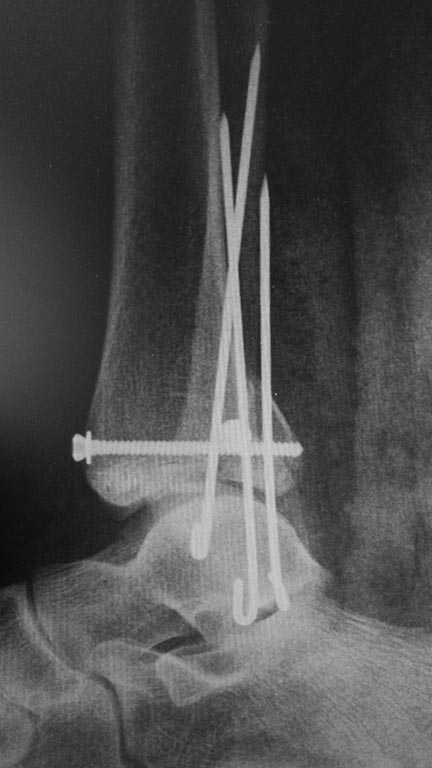

Мужчина, 1987 г.р. получил травму 10.2014. ДТП. Закрытый двухлодыжечный перелом костей костей левой голени, перелом заднего края большеберцовой кости с подвывихом стопы кзади, кнаружи.

Наложен дистрактор. Операция 10.2014: закрытая репозиция, остеосинтез спицами, винтами. В дальнейшем произошло ожидаемое усугубление нарушений взаимоотношений в голеностопном суставе.

Какой план лечения,на Ваш взгляд, предпочтительнее в данном случае? Возможно ли одномоментно устранить подвывих или только на аппарате Иллизарова? Первичные снимки после травмы отсутствуют. Критично ли "растоптана" латеральная суставная поверхность большеберцовой кости?